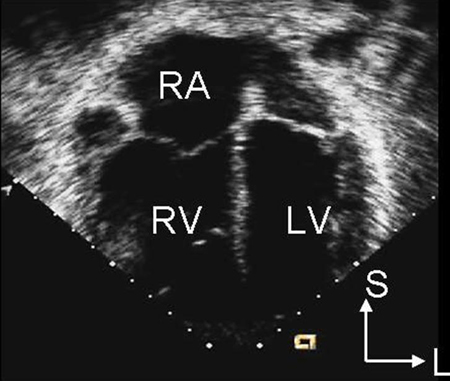

A radiografia torácica não é útil na determinação do subtipo e pode ser normal em um DSA pequeno. O eletrocardiograma (ECG) também pode estar normal no secundum pequeno, seio venoso e DSAs do seio coronário sem teto. Com um desvio circulatório maior, pode haver aumento do átrio direito, hipertrofia ventricular direita ou desvio do eixo direito.[Figure caption and citation for the preceding image starts]: Imagem de ecocardiografia do eixo paraesternal curto revelando um aumento ventricular direito em um paciente com defeito do septo atrial (DSA). (VD) ventrículo direito; (VE) ventrículo esquerdoImagem cedida por Patrick W. O'Leary, MD [Citation ends].